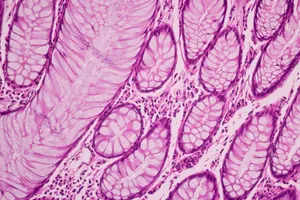

3. 조직 검사 (생검)